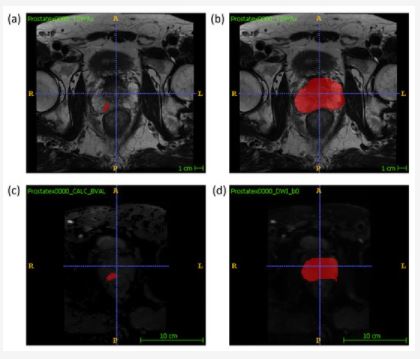

Thus, the main goal of this work “Prediction of Prostate Cancer Disease Aggressiveness Using Bi-Parametric Mri Radiomics” was to develop supervised machine learning models exploiting radiomic features extracted from bpMRI examinations, to predict biological aggressiveness; 288 classifiers were developed, corresponding to different combinations of pipeline aspects, namely, type of input data, sampling strategy, feature selection method, and machine learning algorithm.